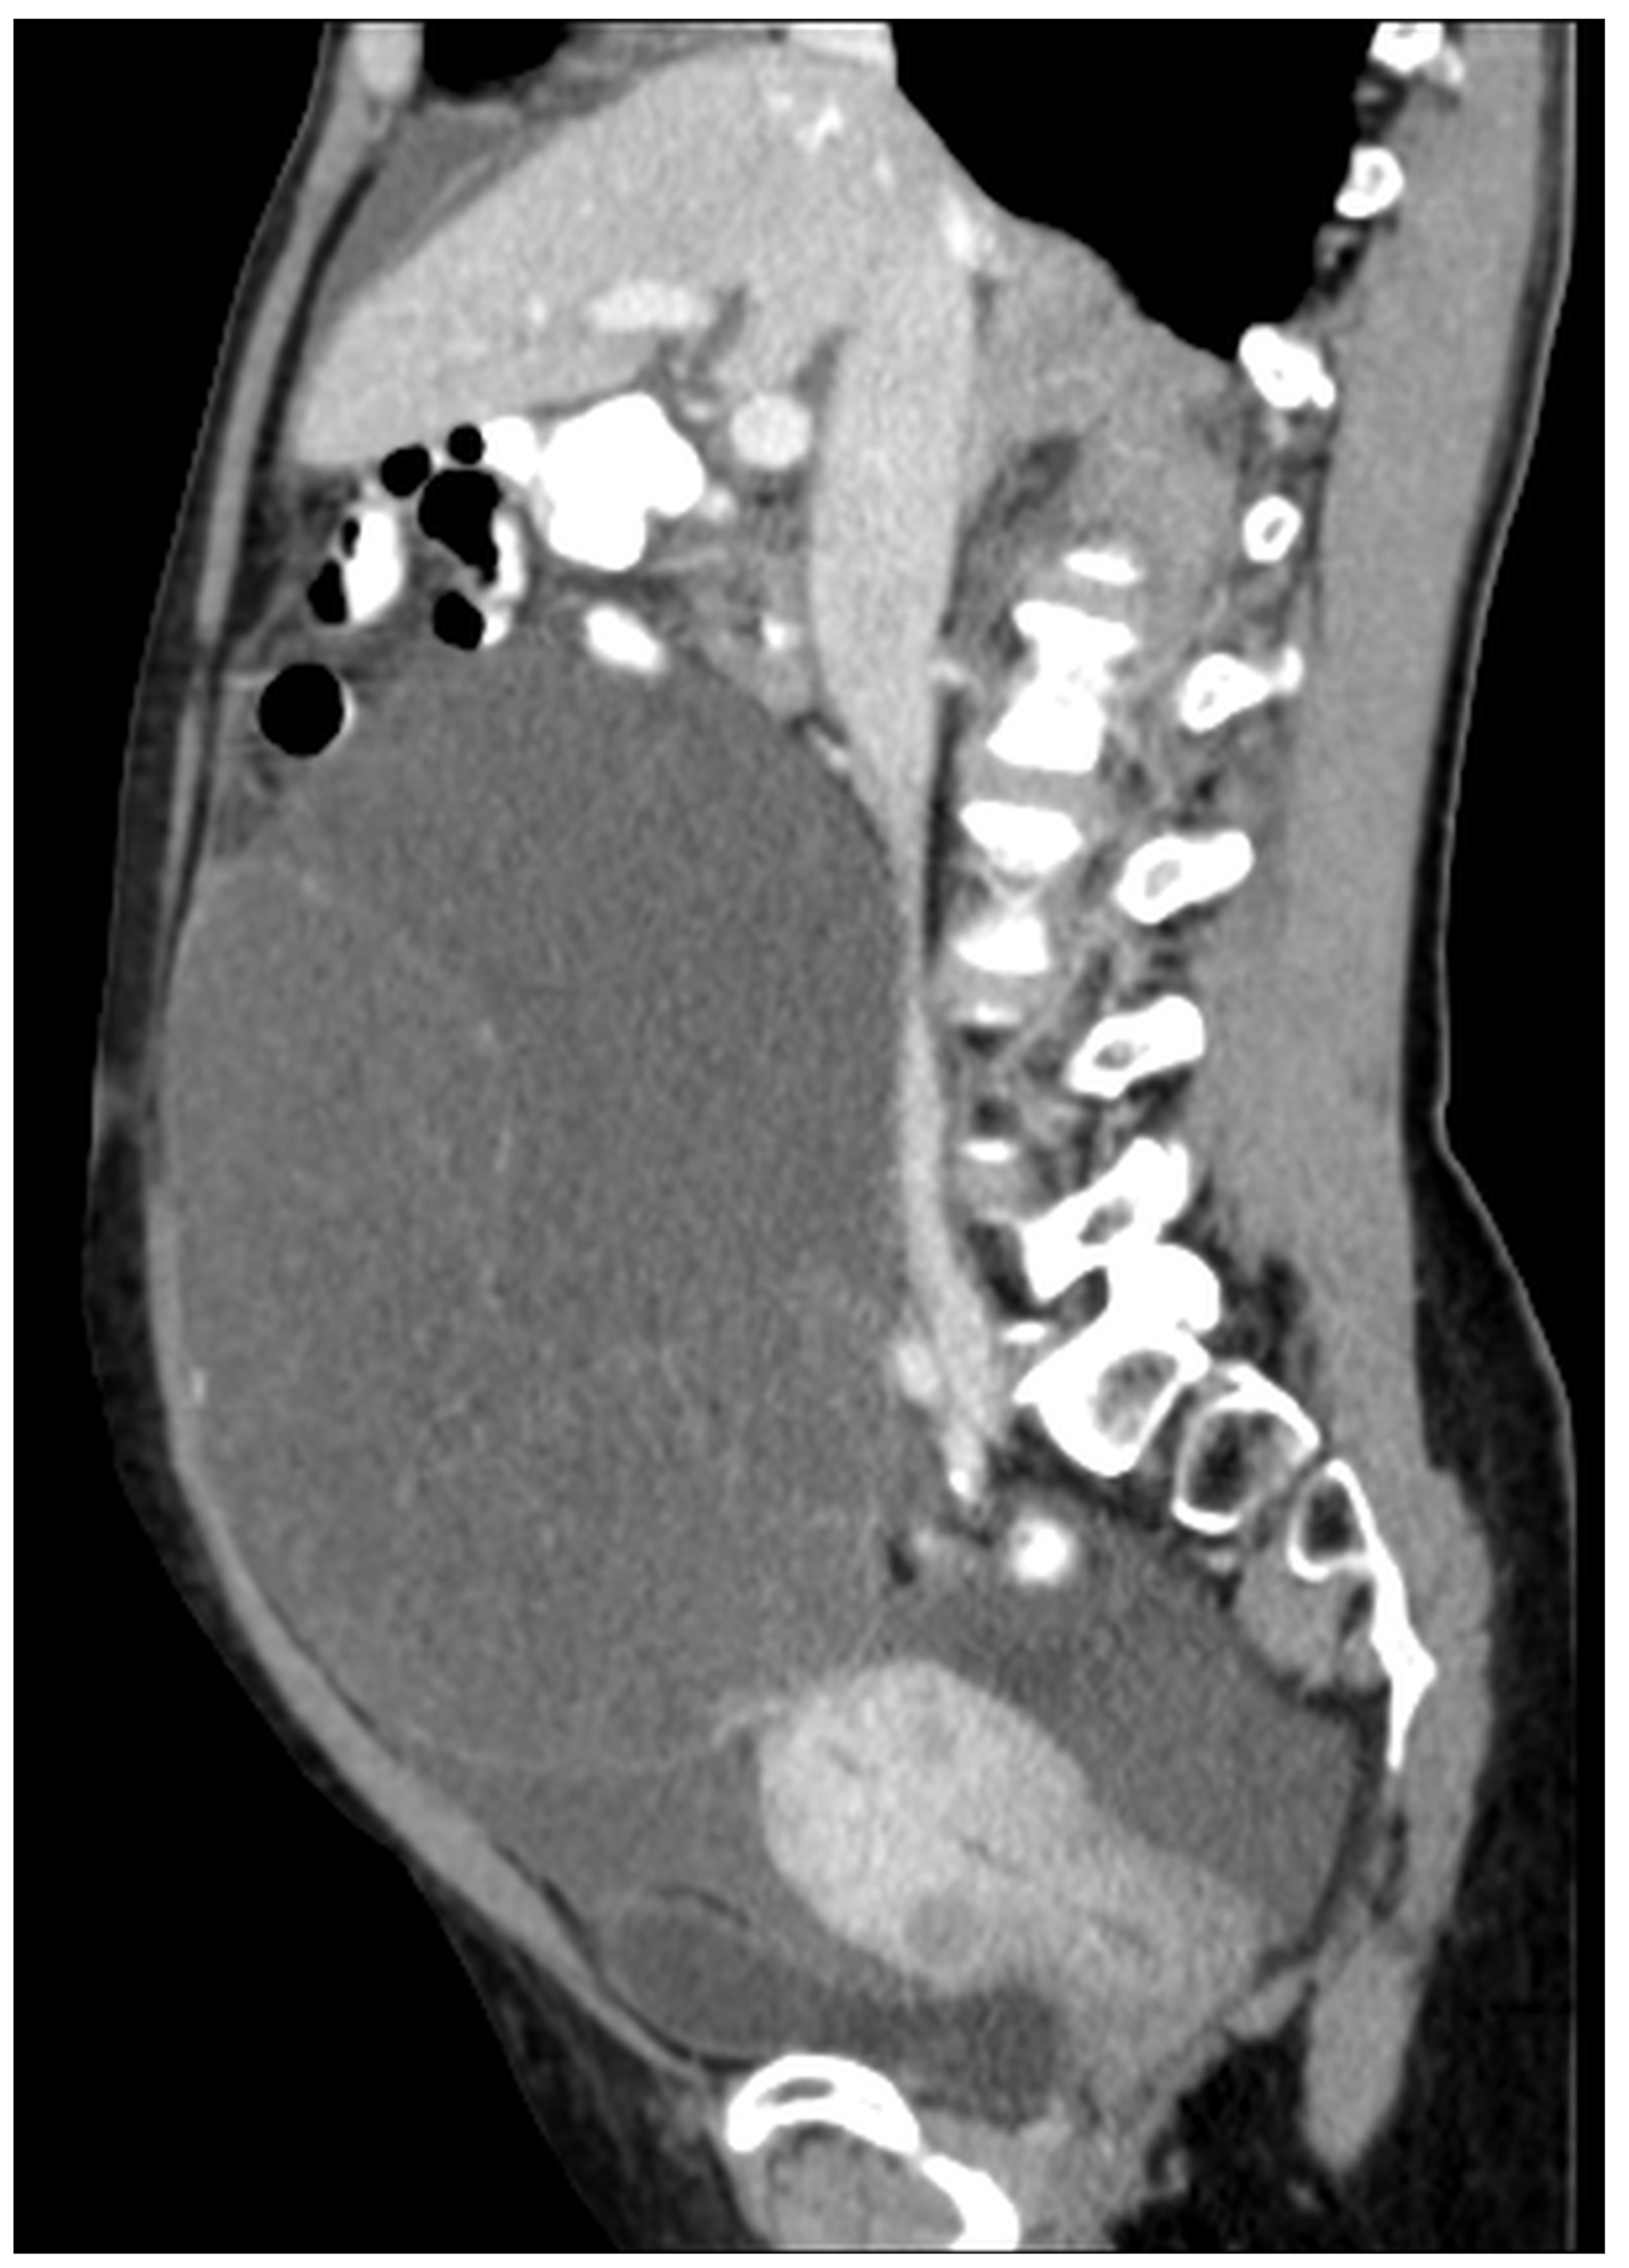

Figure 2. Mucocele of the appendix with calcification in the mucocele’s wall (arrows) (CT, venous phase, sagittal plane). Cystic dilatation of the appendix and calcification in the appendiceal wall. This is a typical sign for a mucocele, and it is present in 50% of patients [9].